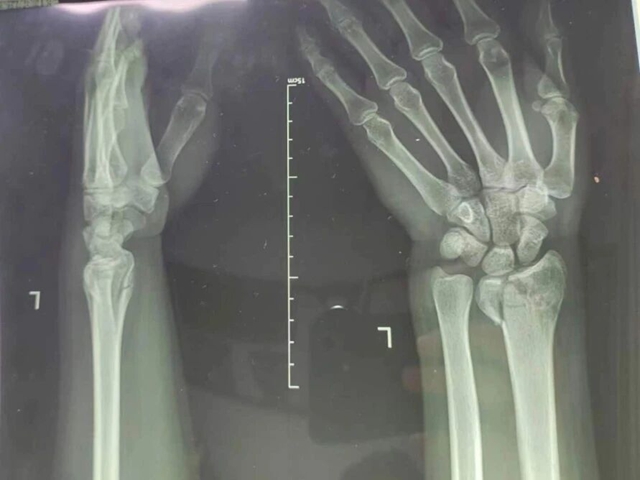

30余岁的李明(化名)在宜宾打球时不慎摔伤,双侧手臂当即疼痛难忍、无法动弹,当地医院检查提示双桡骨远端粉碎性骨折,经手法复位、石膏固定后仍疼痛难忍,为求进一步专业治疗,专程来到西南医科大学附属中医医院就诊。

复位前,患者影像资料